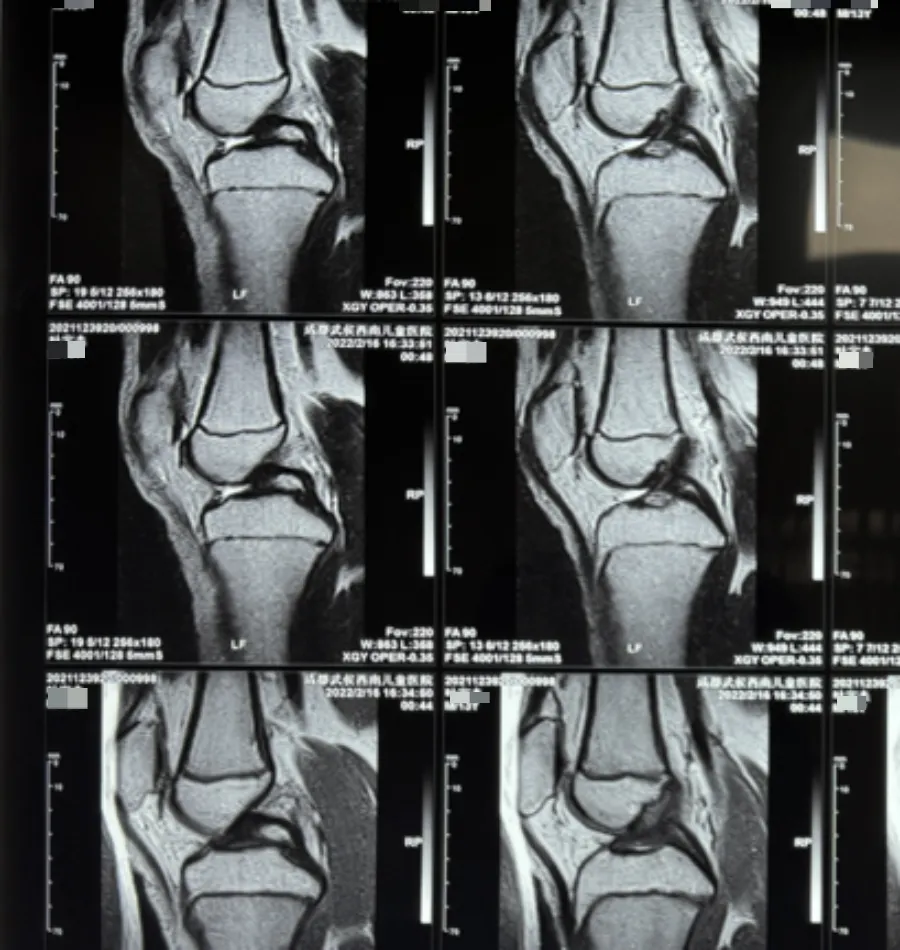

干扰生长激素分泌规律

性正常生长发育中,生长激素分泌与身体发育阶段匹配。

性早熟打破这种平衡,性激素提前大量分泌干扰下丘脑-垂体轴对生长激素分泌的调节,导致生长激素分泌的时间、频率和量紊乱。

△图源|内部素材,请勿转载

初期虽有短暂身高突增,但后续生长动力不足,难以维持正常生长速度,最终影响成年身高。